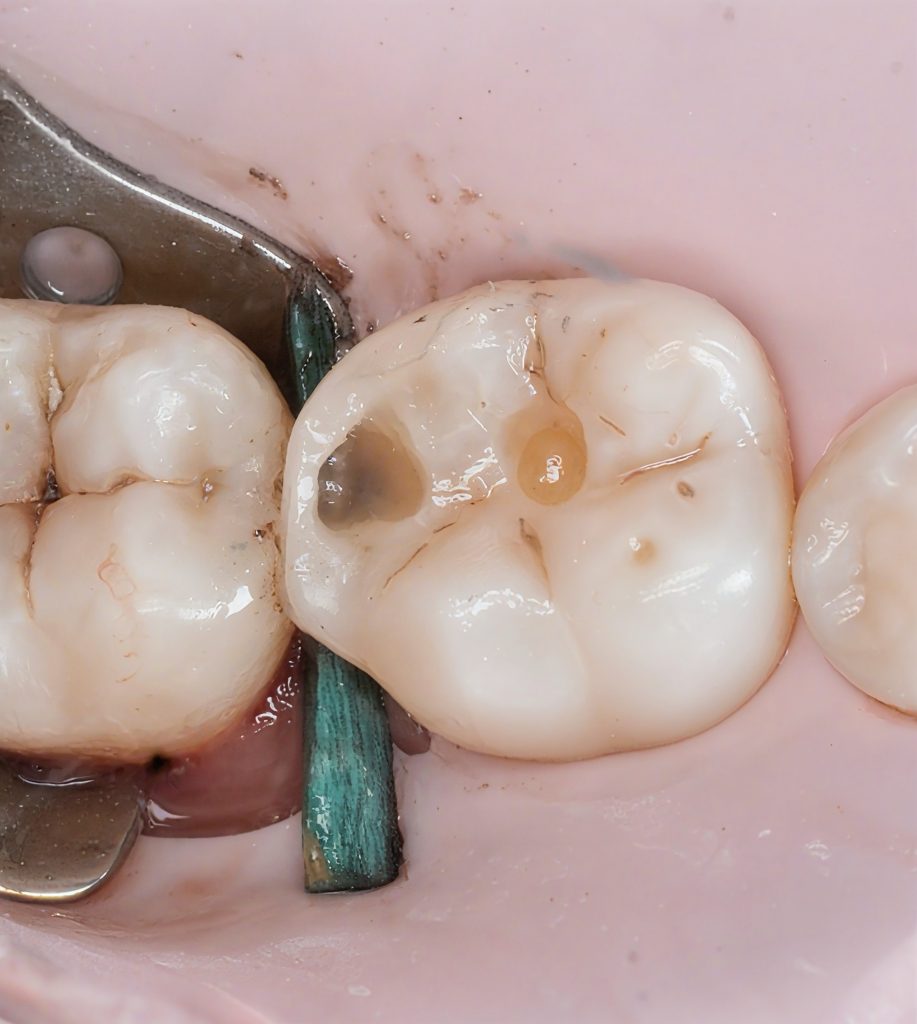

4.3 Matrix Placement & Contact Formation

A sectional matrix with a wooden wedge and separation ring was used.

The key elements:

- matrix positioned flush with the gingival margin

- firm wedge to seal the cervical gap

- ring for slight tooth separation

- ensuring a slight convexity cervically to mimic natural emergence

This combination created the space needed to form a tight, anatomical contact.